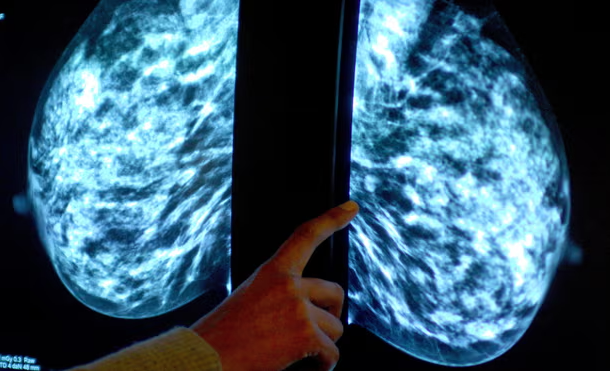

Përdorimi i inteligjencës artificiale në depistimin e kancerit të gjirit rrit mundësinë e zbulimit të sëmundjes, kanë gjetur studiuesit, në atë që ata thonë se është testi i parë i kësaj qasjeje në botën reale.

Studime të shumta kanë sugjeruar që AI mund të ndihmojë mjekët të zbulojnë kancerin por ky është studimi i parë ku AI është përfshirë që në fillim e deri në fund.

Katalinic dhe kolegët e tij analizuan të dhënat nga 461,818 gra në Gjermani, të cilat iu nënshtruan ekzaminimit të kancerit të gjirit midis korrikut 2021 dhe shkurtit 2023, si pjesë e një programi kombëtar që synon gratë asimptomatike të moshës 50-69 vjeç.

Të gjitha u ekzaminuan në mënyrë të pavarur nga dy radiologë. Megjithatë, për 260,739 nga gratë, të paktën një nga ekspertët përdori një mjet AI për t’i mbështetur ato.

Në përgjithësi, 2,881 nga gratë në studim, i cili është publikuar në revistën Nature Medicine, u diagnostikuan me kancer gjiri. Shkalla e zbulimit ishte 6.7% më e lartë në grupin e AI.